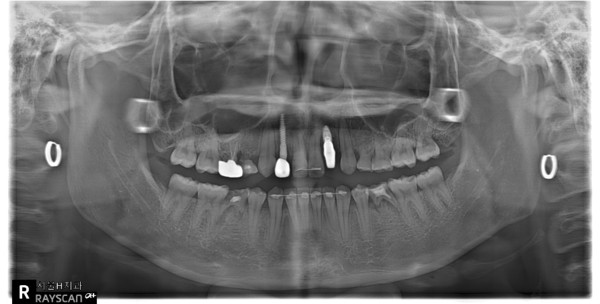

이 환자는 19세 여환으로 multiple congenitalmissing을 가지고 있으나 전치부 반대교합과 spacing의 해결만을 위해 내원하였습니다. 부분교정 시행후 상악 양측측절치 부위를 임플란트로 식립하기로결정하였습니다.

상기 환자의 경우 선천적 결손치부위인 12번과 22번의 공간은 교정으로 확보가 되어 있었으나 수술할 당시에 환자가 내원을 오랫동안 하지 않아 22번 공간에 약간의 relapse가 발생되어있는 상태였습니다.

양측 모두 처음에는 골이식없이 2.5직경의 onebody implant를 식립하였는데 22번의임플란트는 골유착 실패로 제거하게 되었습니다. 다시 마무리 교정을 한 후에 4개월 후 22번에 3.5직경의 임플란트를 골이식과 더불어 식립하였고 최종 보철물을 마무리하였습니다.

확실히 상악 전치부 동일부위에 2번의 수술을 진행하는 경우는 harmonic gingival line을 맞추는 것은 쉬운일이 아니라고 생각됩니다.